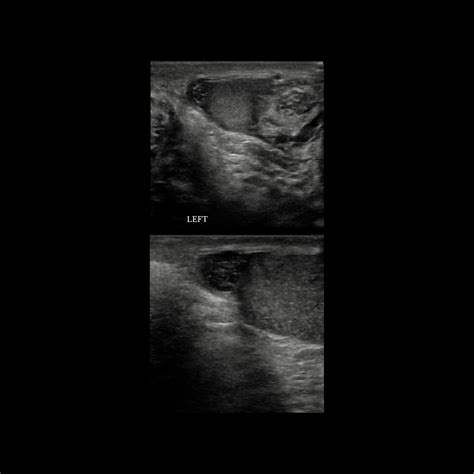

Scrotal Ultrasound (Color Doppler) Evaluating blood flow to the testicle; essential to rule out full testicular torsion.

⚠️ Note: If there is any clinical ambiguity or if the blood flow to the testicle itself appears compromised on ultrasound, an emergency surgical exploration (orchiopexy) is performed to rule out testicular torsion.